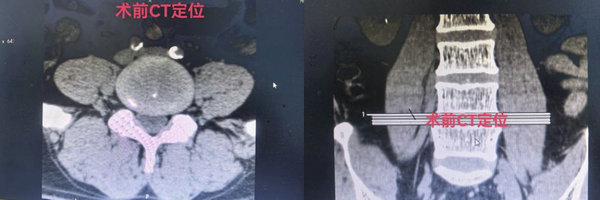

为求进一步诊治,靳先生来到血管外科。科室主任王颖带领专家团队,对其病情进行了全面细致的评估。考虑到患者病史长、下肢缺血及疼痛症状显著,传统治疗方式效果有限,团队经深入讨论,决定为其实施目前国内先进的微创介入技术——经皮腰交感神经射频消融术。

在完善术前准备后,血管外科专家团队为靳先生顺利实施了手术。术中,在先进的数字减影血管造影(DSA)设备精准引导下,穿刺针被准确置入目标神经节附近。通过射频电流产生可控的热效应,选择性地阻断支配下肢的腰部交感神经中,传递疼痛信号的纤维,同时最大程度保留触觉等正常功能。